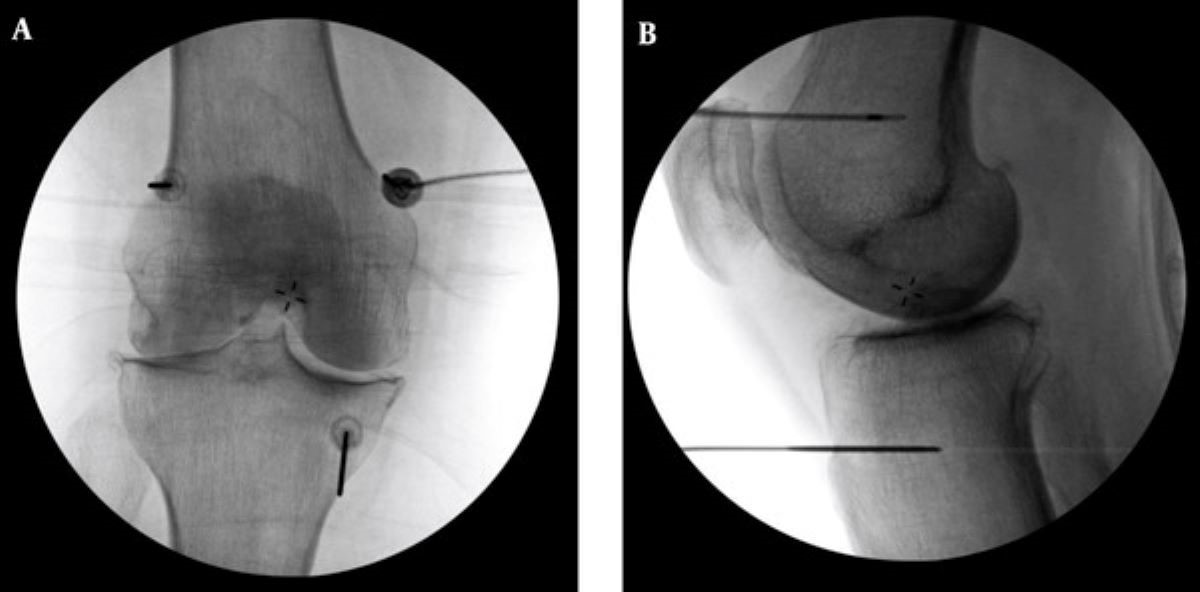

診斷上,退化性關節炎可透過X光查看軟骨縫隙、有無骨刺等,結合身體檢查觀察關節的穩定度、疼痛情況以及是否積水,藉此評估退化程度。原則上,中度以前多能藉由藥物、復健、肌力訓練、生活調整與體重控制改善,中晚期的患者則可能需要置換人工關節,但針對不適合手術或不願手術的患者,則可採用「高頻熱凝療法」止痛。李宜軒醫師說明:「此項技術過往多用於椎間盤突出、滑脫等脊椎神經壓迫造成的下背痛、坐骨神經痛的止痛治療,近來也運用至膝關節退化。執行方式是在局部麻醉的情況下,以X光定位將電極導針導引至膝蓋的三個主要感覺神經叢,確認施行目標後,接上電源線輸出高頻電波,藉由熱能與電效應,使引起疼痛的神經失去傳導疼痛的能力,降低疼痛。」為確保施行過程中未傷及運動神經,治療前會進行不同電量測試,並請病人活動膝蓋,在確定不影響日後活動的情況下進行治療。一般而言,效果會在術後當下至一週內顯現,普遍可維持半年至一到兩年,因人而異。但若有急性感染、心律調節器或正在服用抗凝血劑者即不適用此治療,需由醫師進行評估。

高頻熱凝療法以X光定位將電極導針導引至膝蓋的三個主要感覺神經叢,藉由熱能與電效應,麻痺痛覺神經。